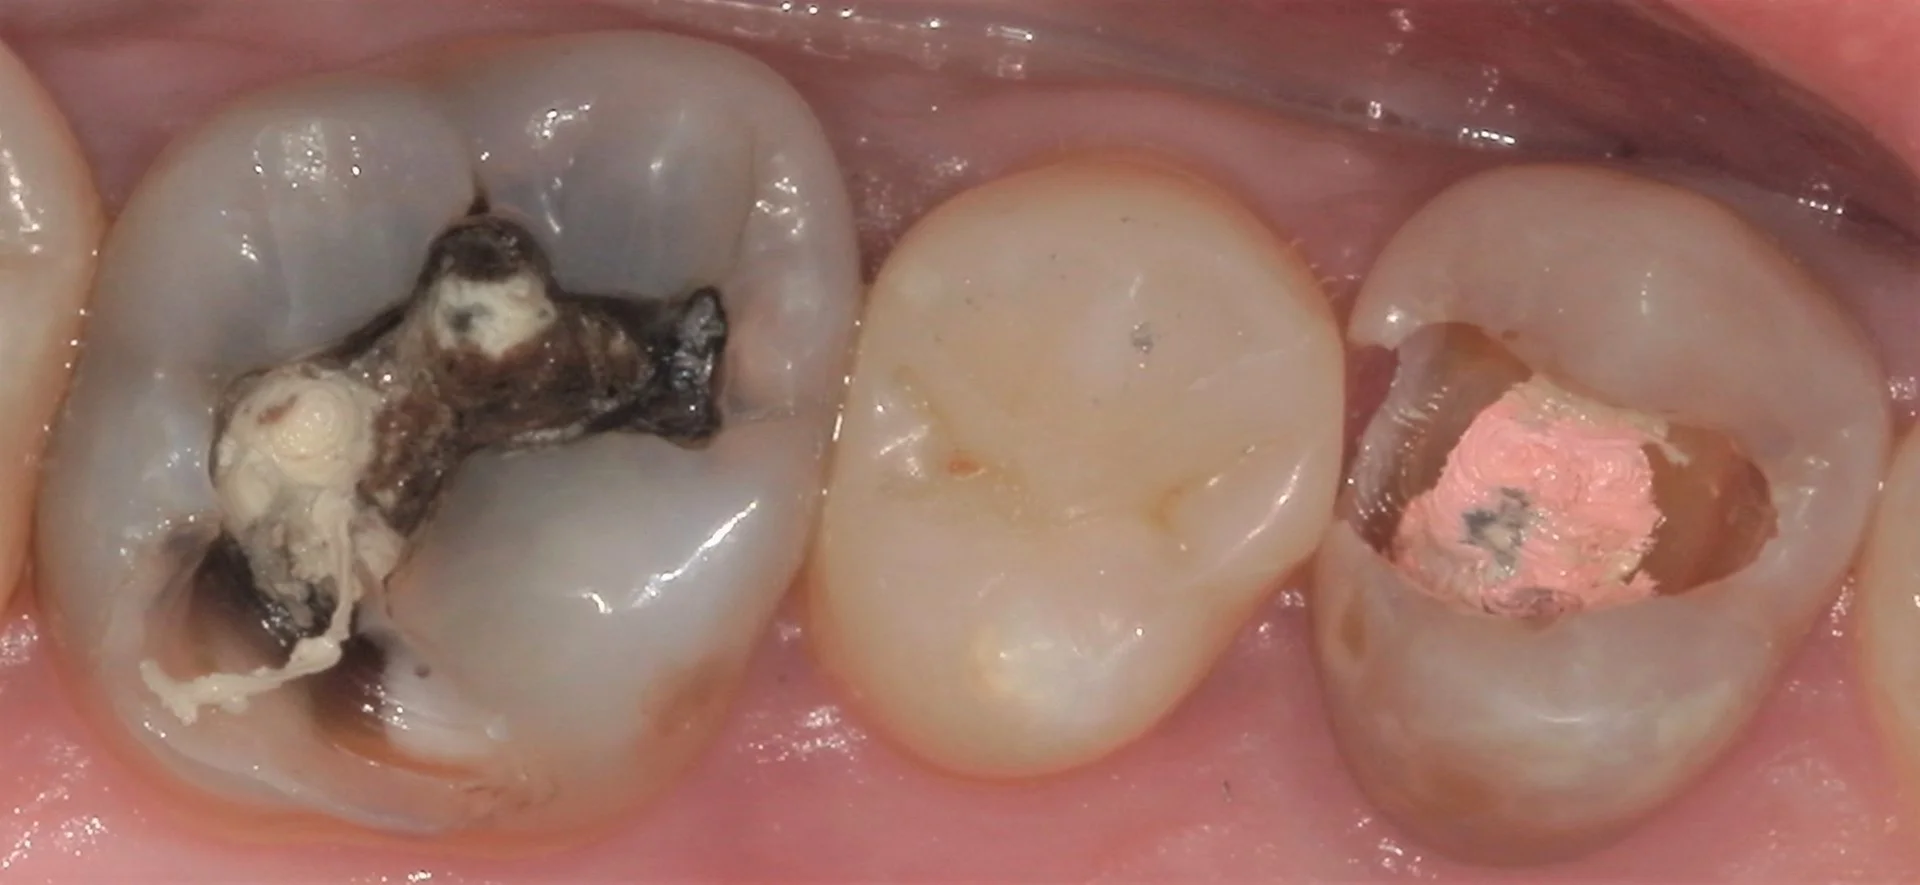

では術前の写真からです。

こちらの写真の中で実は最も神経に近かったのはレントゲン診査上、真ん中の歯でした。

そのため、本日は真ん中の歯のみ治療し、後日前後の歯を治療するという治療計画に変更いたしました。

まず古い詰め物を取って虫歯を見やすくしたのが、こちらです。

こう見るとかなり内面が黒く虫歯になっているのが分かるかと思います。

前後の歯の間にまで進行していましたので、そこら辺も全部除去したのがこちらです。

その時に虫歯を見やすくしたのが、こちらの写真です。

画面左側の歯はレントゲンで見るよりも遥かに内面で大きくなっていましたね。

そして画面右側の神経の治療の際に詰めるピンクの薬が見えている状態です。

神経の治療後、私も詰め物で終わらせることは多々ありますが・・・

その際、このピンクの薬はこれほど大きく見える状態ではなく、ある程度除去しておいた方が予後が良いです。

というのも、このピンクの薬は白い詰め物はくっつかないですし、これに感染が生じると根の先に膿が溜まってしまう事もあります。

その為、再度虫歯になってもピンクの薬に細菌が到達しづらいように根の管の内面にまで除去しておいた方がその後の予後が良くなるんです。

虫歯やピンクの薬を除去したのが、こちらの写真です。

分かりづらいですが、根の管の大体2~3mmくらいまで削り込んでます。

これをするとしないとで感染リスクが大きく変わるので、歯科医師の方は是非気を付けて頂きたい部分でもありますね。

そして画面左側の歯については内面がほぼ無い状態になっていました。

噛むと割れてしまいそうなクラックのある部分・最低限の厚みを残した状態がこのくらいでした。

どちらの歯も表面のエナメル質の部分しか残存していないので、次駄目になったら流石に被せ物にせざるを得ない状況ですね。